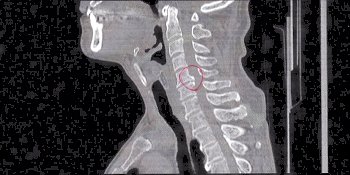

とりあえずCTスキャン。

で、頂きましたのが、その一部のこれらの画像なんです(^.-)☆

特に痛みの原因となるようなモノは見当たらず、強いて言えば『老化現象』との事でありました。